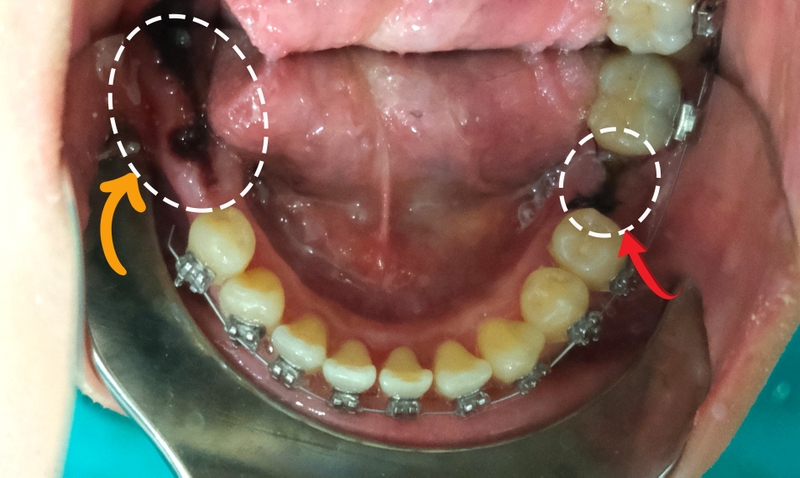

Những trường hợp khác, mất răng số 7 vẫn niềng được nhưng cần trồng răng trước khi niềng. Hiện nay, có 2 phương pháp để phục hình răng số 7 bị mất gồm:

Mất răng số 7 có niềng răng được không? Theo các chuyên gia thì hoàn toàn có thể. Tuy nhiên, trước khi niềng răng, nha sĩ cần phục hình răng số 7. Vì vậy. kỹ thuật niềng răng khi mất răng số 7 sẽ phức tạp hơn bình thường. Một số bước chính trong quy trình niềng răng khi mất răng số 7 diễn ra như sau: